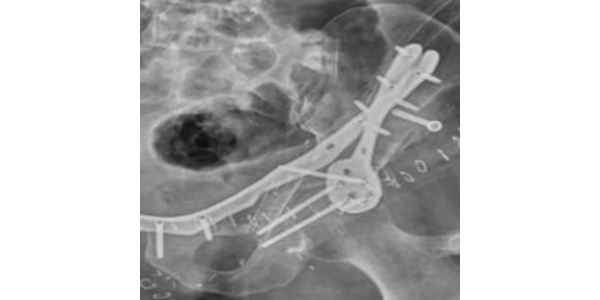

Dr. Manish Agarwal, India’s leading Onco Orthopedic surgeon in Mumbai, Maharashtra being a pioneer in using treated tumor bone/ECRT as a method of reconstruction aided surgeries studied medical history, imaging and histopathology reports. It was decided to proceed with ECRT line of treatment. Salvage of acetabulum with ECRT is more of challenging procedure due to complex anatomy of hip, limitation on access due to vital organs in pelvis and particularly due to functionality of load bearing joint. Hence Dr. Manish Agarwal decided to use patient specific cutting guide and patient specific anterior and posterior plate to fix radiated bone fragment back to the position to give maximum functional benefit to the patient. 3D Incredible team discussed with Dr. Agarwal, the designing and entire manufacturing process. Read more

Implant was manufactured under ISO 13485 guidelines & tested to give an accurate fit & utmost safety.

Cutting guides and jig from 3D Incredible helped the surgeon to give an accurate cut and complete the surgery in one go. Once the resection was done, customized plates from 3D Incredible was implanted. Plates were manufactured using Ti6Al4VELI, a biocompatible material; Read more